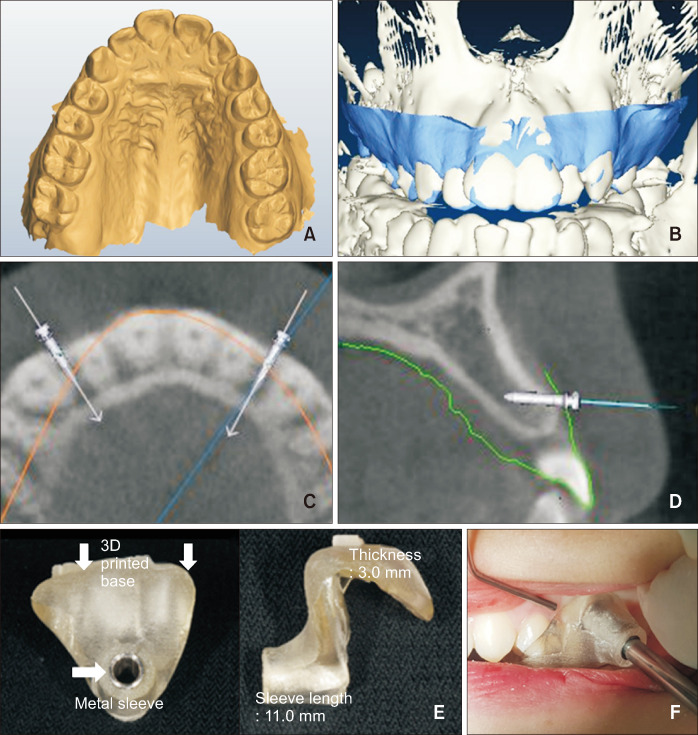

Objective: To assess the success rate and proximity of miniscrews to the root using surgical guides produced by integrating data obtained from cone-beam computed tomography and intraoral scanned models.

Methods: This retrospective study involved 113 patients (224 miniscrews) who underwent miniscrew placement as part of their orthodontic treatment. Two operators placed miniscrews between the buccal alveolar bone of each patient and assessed initial stability by measuring the Periotest value (PTV) and insertion torque (IT). Patients were divided into two groups based on the miniscrew insertion method: manual group (MG) and surgical guide group (SG). Root proximity was assessed using periapical radiography, and miniscrews that remained in place for over 6 months were considered successful.